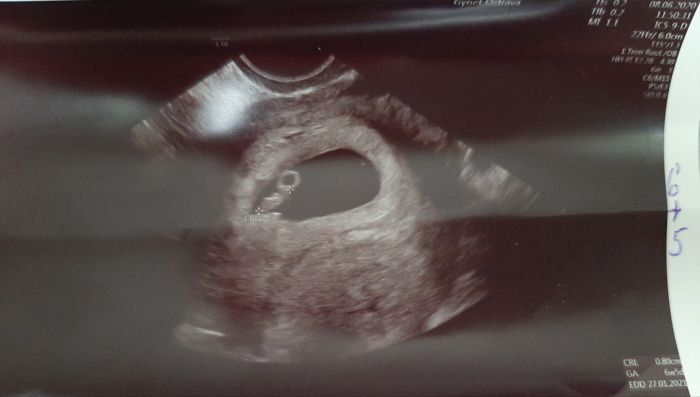

Tak mam po kontrole a videla jsem srdicko a bobika

Ma 7 mm hihi

Prikladam foto (to kolecko.je placenta a ja myslela ze hlava

A zbytek je bobik

)